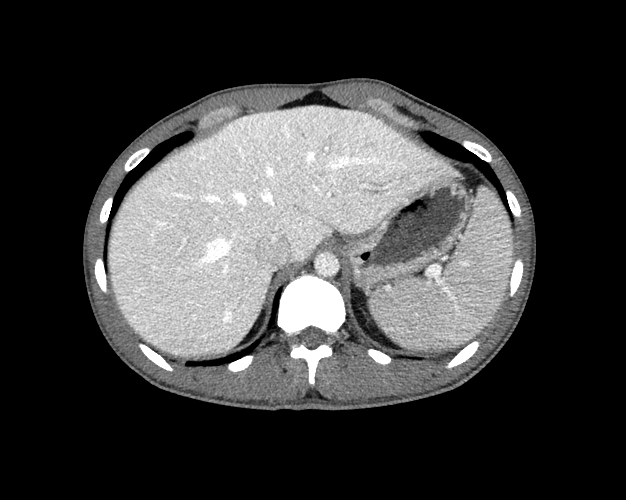

Body

Covers abdominal CT anatomy.